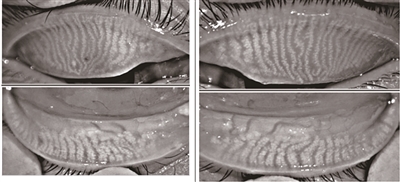

健康睑板腺(红外成像)